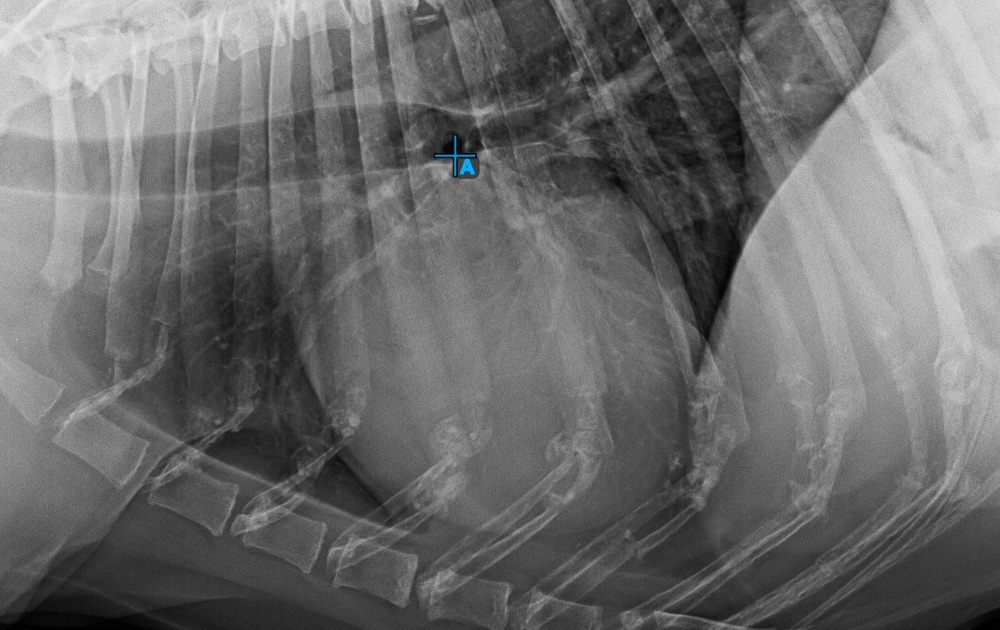

Complete the long axis of the heart by marking the Apex point, near the bottom of the heart.

The image below represents a typical placement of the Apex point.

../../_images/image394.jpg